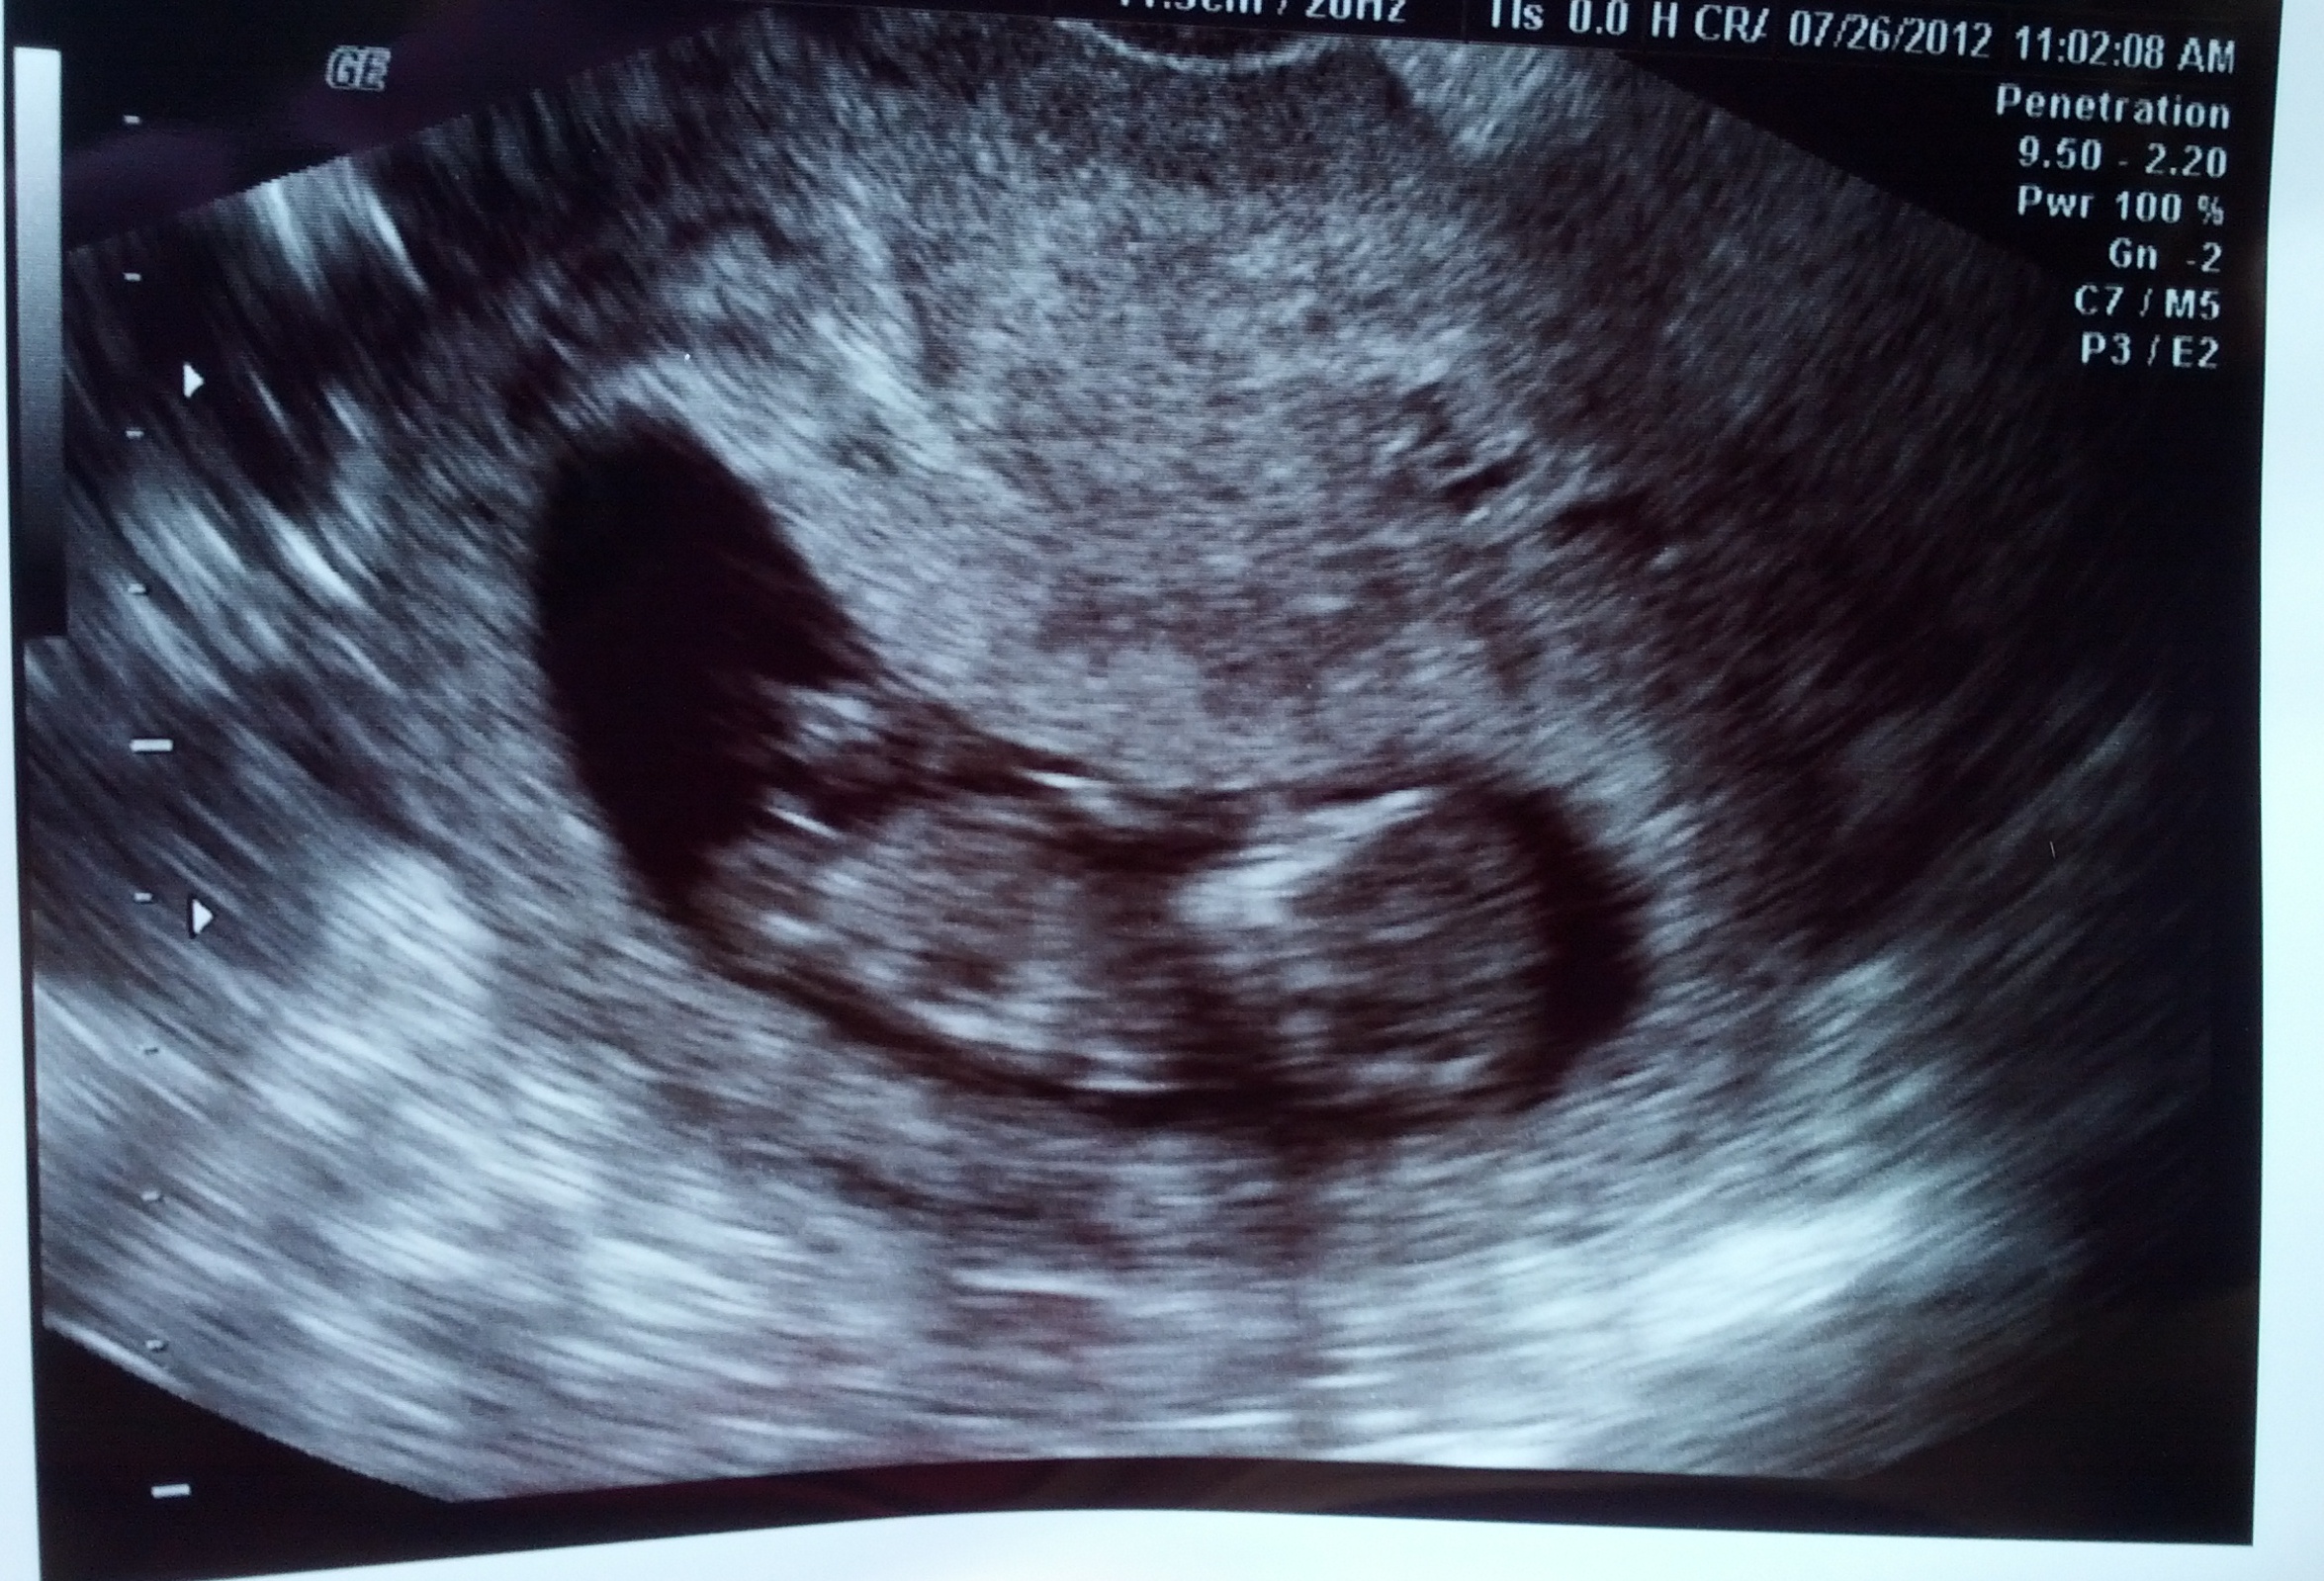

The tech told me the baby was not in profile view...but I've had a couple people tell me they think it is in profile. The nub is very visible, but I"m not sure if it's a reliable position to guess from? Please give me your honest opinions of what direction the baby is facing and whether a nub guess is possible...Thank you!!!

Attachment 3945